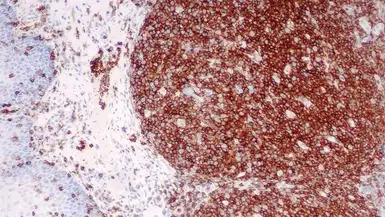

IHC-P analysis of human tonsil tissue using GTX01850 CD45 antibody [X16/99].